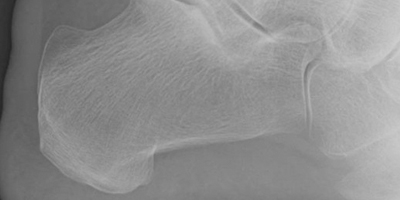

Fracturas La articulación del tobillo une la pierna con el pie y es la que ...